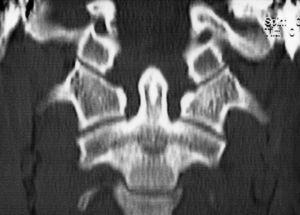

Mujer de 16 años con historia por tortícolis fija aparecida tras cirugía tiroidea; tratada mediante AINE y ortesis cervical blanda, no mejora por lo que a las 10 semanas es enviada a nuestro centro. El diagnóstico, SRCAA tipo I de Fielding, se obtuvo mediante TAC (fig. 6A) con reconstrucción tridimensional (fig. 6B) utilizándose el mismo protocolo de tratamiento que en los otros pacientes, llegando a 14 kg; a las 3 semanas la movilidad era simétrica y la TAC confirmó la reducción completa de la divergencia rotacional (fig. 7), inmovilizándose con halo-yeso 6 semanas y ortesis cervical blanda otras 6 semanas. Dos años después, la función es completamente normal, no habiendo presentado episodios de cervicalgia ni tortícolis.

Figura 6. A: tomografía axial computarizada convencional en la que se puede apreciar la rotación de 32° entre C1-C2 en el paciente n.O 3. B: la reconstrucción tridimensional nos muestra la deformidad típica de rotación y pinzamiento C1-C2.

Figura 7. Imagen de tomografía axial computarizada correspondiente a la tercera paciente, que muestra la correcta reducción tras tres semanas de tracción.